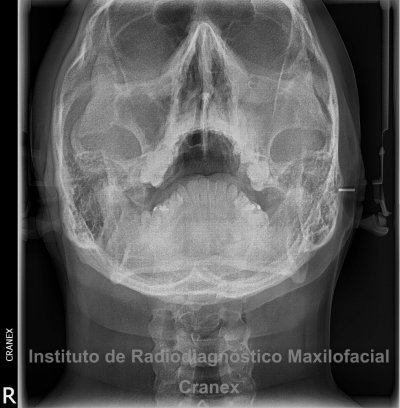

Caso Radiográfico N° 06: Sinusitis de seno maxilar en relación a comunicación buco sinusal

Paciente de 23 años de edad de sexo masculino, que acude a nuestra institución para estudio radiográfico de senos maxilares, refiriendo haber sido sometido a la extracción de la pieza 2.6 hace varios días (no indicando la fecha exacta de la extracción dental), así mismo refiere dolor vago, sensación de obstrucción del lado izquierdo de la cara y aliento fétido.

A la evaluación de las radiografías Panorámica, Waters, y radiografía Periapical, observamos, neumatización alveolar y opacificación parcial de seno maxilar izquierdo, lecho alveolar de correspondiente a pieza 2.6, con discontinuidad de la cortical de la pared basal de seno maxilar adyacente, y engrosamiento de la membrana antral de seno maxilar ipsilateral. Signos radiográficos compatibles con proceso inflamatorio sinusal (Sinusitis) en relación a comunicación buco sinusal.